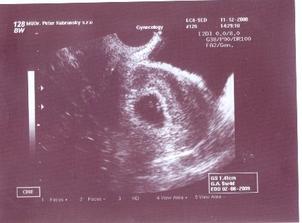

11.12.2008 potvrdené lekárom 6tt+4 + sono

15.01.2009 nás čaká ďalšie sono:D, už teraz sa teškáme....08.01.2009 špinenie, panika...tak šups doktorovi - predpísal nám Utrogestan, MagneB6 a Ascorutin. Máme si dávať denne dva citróny a dve lyžičky medíku. Dostali sme štipľavú injekciu, ale bábätku našťastie veselo bije srdiečko...a máme pre istotu aj fotečky:D